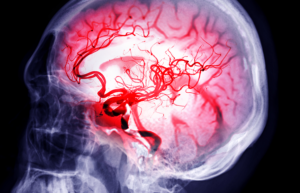

Stroke Outcomes Mediated by These 2 Mechanisms